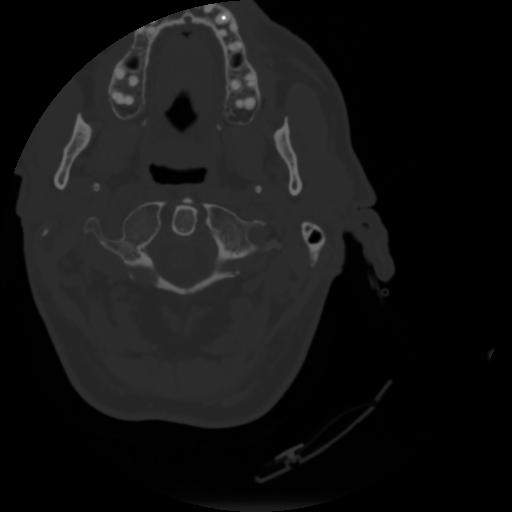

4 CEREBRO,,Vol,0.5,CEREBRO,,